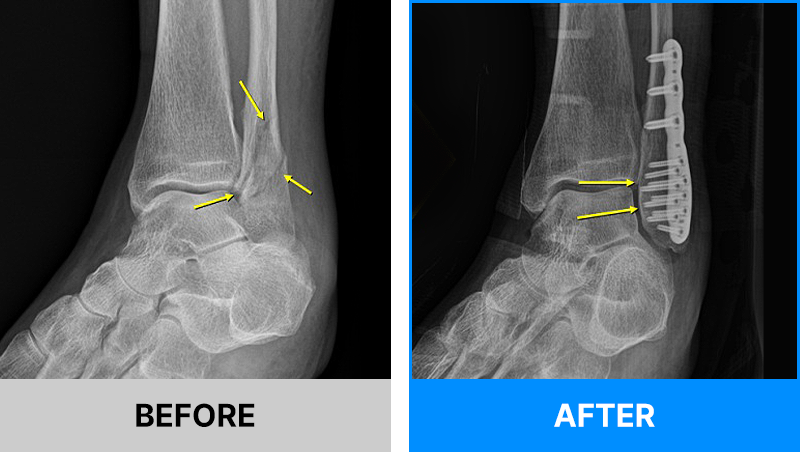

왜 당일 입퇴원 수술일까요?

오래 입원할 필요가 없기 때문입니다.

서울거탑정형외과에서는 전신마취, 척추마취가 아닌

국소부분마취(신경차단) 및 수면 마취를 통해 수술을 시행합니다.

수술 가능 여부 확인은 대표원장과의 진료가 필요합니다.